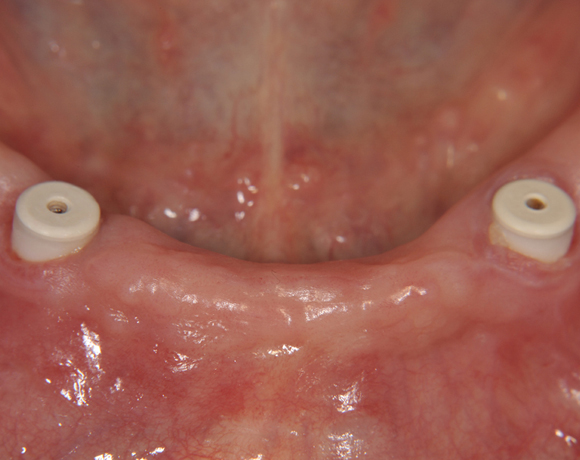

Bild 01: Eingeheilte und freigelegte Zerameximplantate mit Einheilkappen